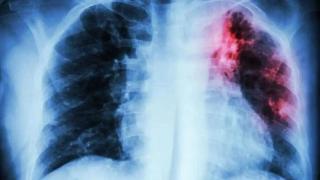

El oncólogo español que estudia por qué surgen nuevos tumores al superar el cáncer del pulmón: "Los pacientes siguen fumando"

Mariano Provencio ha publicado un reciente estudio en el que analiza el riesgo de aparición de un segundo tumor tras haber superado un cáncer de pulmón.

La supervivencia de los pacientes con cáncer de pulmón ha mejorado de una manera que parecía impensable hace unos años.

Aun así, las cifras en España siguen siendo bajas: solo el 30% de los diagnosticados seguirá vivo a los cinco años.